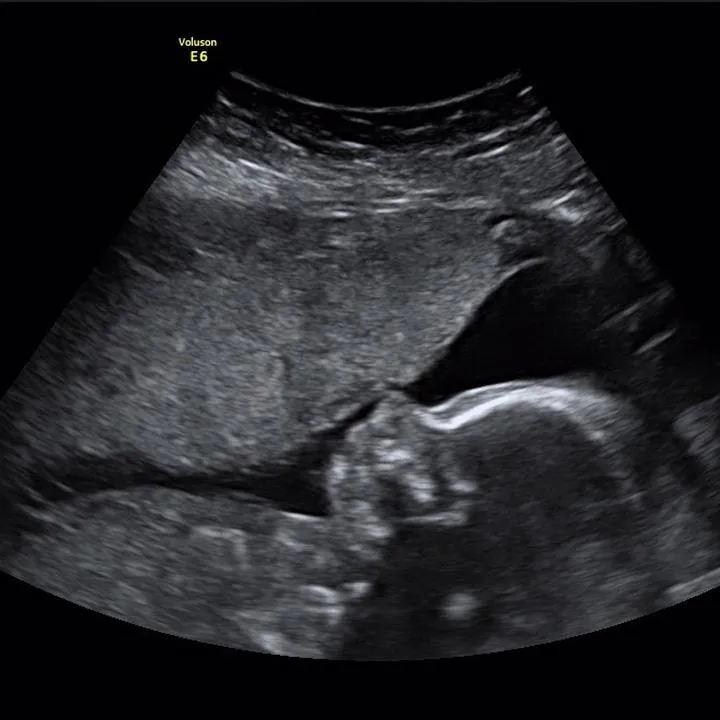

Gdy już zgubimy się w zawirowaniach dat, wówczas przychodzi czas na badanie USG, które uznaje się za znacznie dokładniejsze. Specjaliści wykonujący ultrasonografię zmierzą długość ciemieniowo-siedzeniową płodu, znaną jako CRL. To właśnie wcześniejsze USG pozwala na zminimalizowanie błędów. W idealnym scenariuszu warto przeprowadzić to badanie przed 10. tygodniem ciąży, gdy maluchy rosną w dość jednolitym tempie. Jednak jak to zwykle bywa, im później wykonasz USG, tym więcej problemów, ponieważ każde dziecko może rozwijać się w różnym tempie. Możemy zauważyć, że jedno dziecko znajduje się na innym etapie rozwoju niż drugie. Dlatego lekarze porównują dane z USG z datą miesiączki, co niejednokrotnie wywołuje zawrót głowy u przyszłych mam.

Nie można zapominać, że CRL to nie jedyny wskaźnik, który odgrywa rolę w USG, tylko do pewnego momentu. W miarę postępu ciąży do pomiarów dołączają inne parametry, takie jak wymiar główki (BPD) czy długość kości udowej (FL). To trochę jak gra w szachy: potrzebujesz zestawu ruchów, aby strategicznie ustalić termin porodu. Kiedy wyniki USG i data ostatniej miesiączki zaczynają wykazywać pewne różnice, lekarze mają świadomość, że USG staje się bardziej wiarygodne. Pojawia się więc pytanie: co dalej? Otóż to po prostu oznacza, że maluch może być większy lub sytuacja ciąży jest nieco bardziej skomplikowana, niż się wydawało. Najlepiej zatem połączyć dane z obu metod i czekać na nasze maleństwo z otwartymi ramionami, gotowe na wszelkie niespodzianki!

Drugim istotnym czynnikiem są dane, które lekarz analizuje. Pomiar długości ciemieniowo-siedzeniowej (CRL) stanowi klucz do oszacowania wieku płodu na początku ciąży, jednak w miarę jak maluszek rośnie, zaczynają mieć znaczenie inne parametry, takie jak dwuciemieniowy wymiar główki (BPD) czy długość kości udowej (FL). Oczywiście można się dziwić, że im więcej maluchy rosną, tym więcej parametrów trzeba mierzyć! W tym momencie wkrada się mały chaos, ponieważ niektóre dzieci mogą mieć długie nogi, podczas gdy inne mogą nieco odstawać od normy. Te różnice mogą prowadzić do tzw. „spóźnionych” pomiarów, co z kolei generuje nieporozumienia w określeniu terminu porodu.